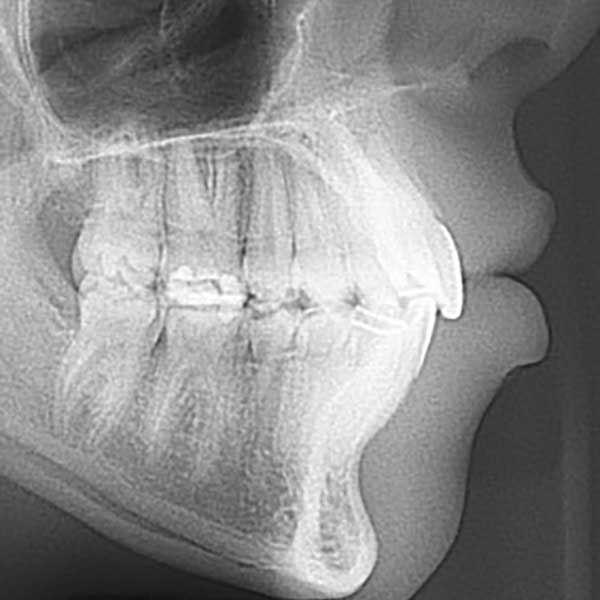

AFTER

Protruded upper anteriors – fixed metal braces

After examining the case, I found that the upper of her front teeth were 8 mm of her lower front teeth, which is a large distance (normal to be 1 to 2 mm). The parents refused the option of tooth extraction, because of her young age, so I solved the problem without extraction because the main problem was caused by the retraction of the lower jaw I fixed it simply with a functional device